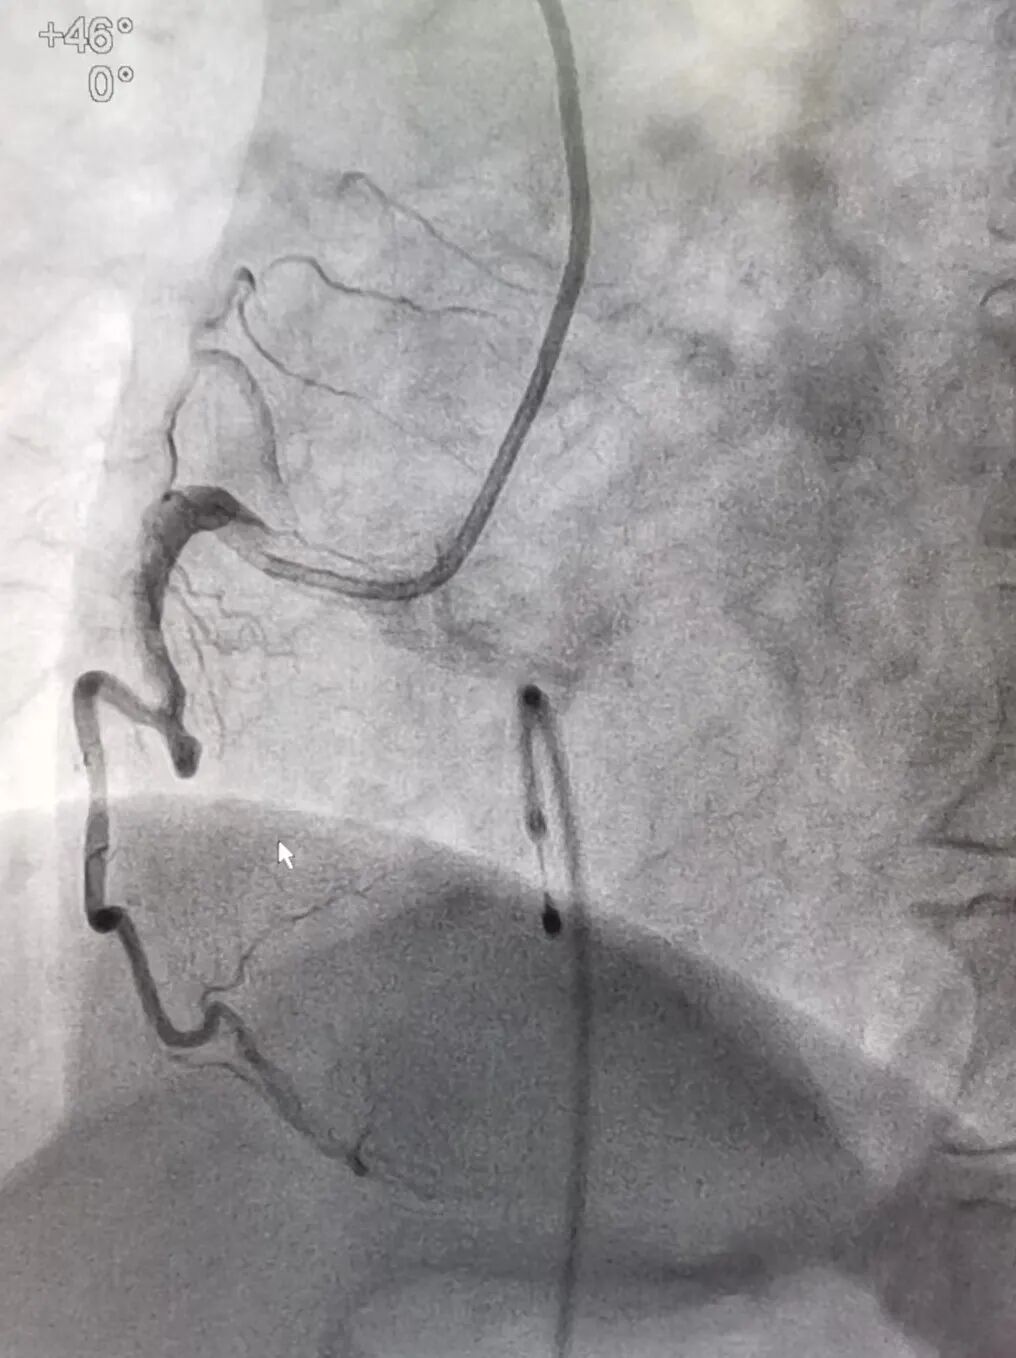

患者存在急性ST段抬高型心肌梗死,想要逆转“电风暴”,必须马上实施急诊冠脉造影检查,开通心脏闭塞血管。胸痛中心团队已全部准备就绪,很快,在呼吸机和临时起搏器的支持下患者被送入导管室。陈桂坚主任医师与郑林立主治医师先为患者行冠状动脉造影,造影提示:右冠状动脉中段急性完全闭塞。团队凭借丰富的经验及精湛的技术,快速开通闭塞的冠状动脉血管,完成支架植入,血管通了。顺利完成手术后,患者被转入ICU继续接受治疗,第7天成功脱离呼吸机、拔除气管插管。第8天病情稳定转回心血管内科病房。经过医护人员的精心治疗,患者目前已康复出院。